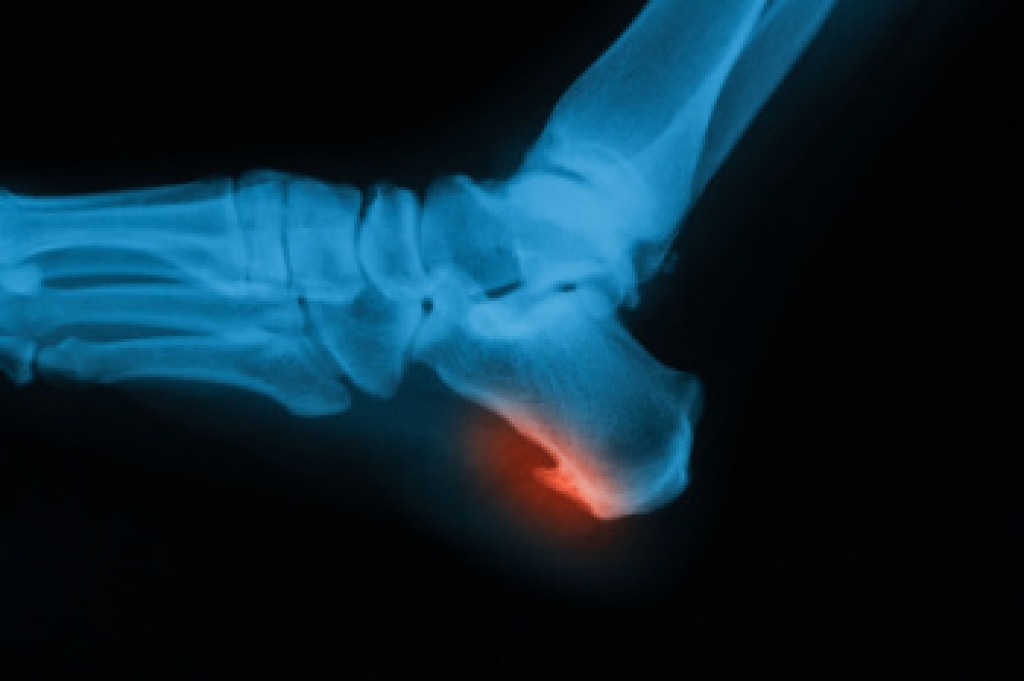

Heel spurs are bony growths that can form on the underside of the heel bone, often associated with plantar fasciitis. These spurs develop over time as a result of repetitive stress or tension on the foot. The primary cause is the strain placed on the plantar fascia, a thick band of tissue that connects the heel to the toes. As this tissue is repeatedly stretched or stressed, calcium deposits may accumulate, leading to the formation of a heel spur. Common symptoms include sharp pain in the heel, particularly when walking or standing after rest. Swelling and tenderness surrounding the heel area may also occur. Although heel spurs are often painless, they can cause significant discomfort and restrict normal movement if left untreated. If you have heel pain, it is suggested that you contact a podiatrist who can accurately diagnose a heel spur, and offer appropriate relief and treatment solutions.

Heel spurs are formed by calcium deposits on the back of the foot where the heel is. This can also be caused by small fragments of bone breaking off one section of the foot, attaching onto the back of the foot. Heel spurs can also be bone growth on the back of the foot and may grow in the direction of the arch of the foot.

Older individuals usually suffer from heel spurs and pain sometimes intensifies with age. One of the main condition's spurs are related to is plantar fasciitis.

The pain associated with spurs is often because of weight placed on the feet. When someone is walking, their entire weight is concentrated on the feet. Bone spurs then have the tendency to affect other bones and tissues around the foot. As the pain continues, the feet will become tender and sensitive over time.